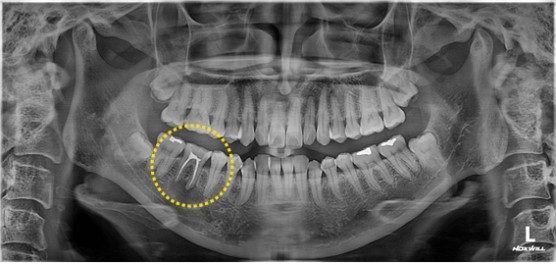

2023. 05. 16

이미지

그동안 증상도 있었고, 불편감이 있어 보철 마무리는 여유를 두고 하였습니다. 3달이 지났음에도 병소가 그대로 있어 좀 아쉬웠었습니다. 경과가 좋으면 1~2 달 이후에도 병소 부위 뼈가 차는 것이 확인이 되기도 합니다.